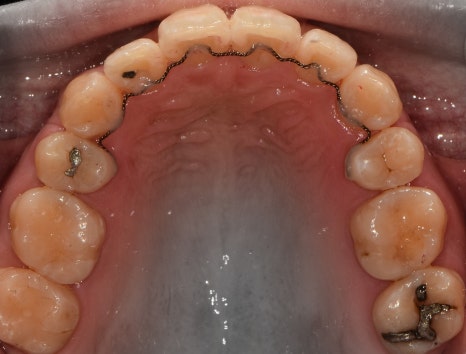

측면에서는 크게 2가지를 느낄 수 있습니다.

- 전치부 치아들의 치축, 전방 뻐드러짐

- 1치대 1치의 관계

*정상이라면, 1치대 2치의 관계를 가져야 됩니다.

또한, 측절치 및 송곳니의 총생들도 같이

관찰을 할 수 있습니다.

앞서, 1치대 1치 관계에 있던 교합관계들이

1치대 2치의 관계로 바뀐것을 볼 수 있으면서

길쭉하게 느껴졌던, U shape 형태의 악궁이

딱 보기 좋은, U shape 로 바뀌었죠.